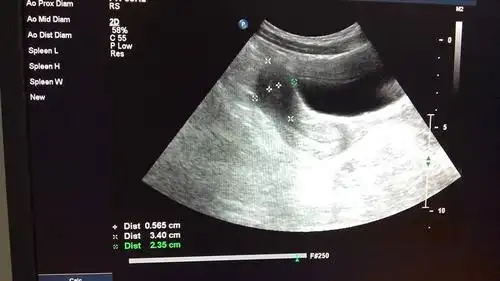

幼稚子宫吗.幼稚子宫#b超检查 在青春期前的任何时期,子宫 - 抖音

这是幼稚子宫吗?对生育有影响吗?

幼稚子宫的诊断

盆腔超声检查如图最可能的诊断是a幼稚子宫b双子宫c双角子宫d